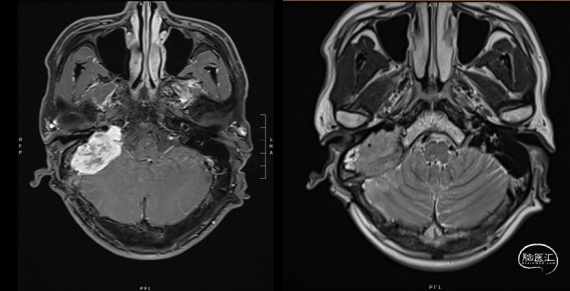

图1. 头颅MRI

右侧桥小脑角区可见团块状稍长T1稍长T2信号影,DWI未见明显受限,周围可见脑组织水肿,范围约37mm*22mm*34mm,界尚清,增强呈明显均匀强化,可见脑膜尾征,相应骨质增厚,相应小脑及脑干受压,第四脑室受压。